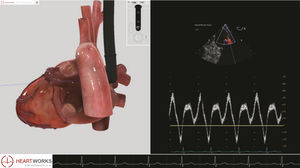

... Los módulos de patología de HeartWorks para la TTE y la TEE han sido creados para facilitar la evaluación ecocardiográfica de pacientes con alteraciones estructurales y hemodinámicas. Este módulo incluye ...

Inventive Medical Limited